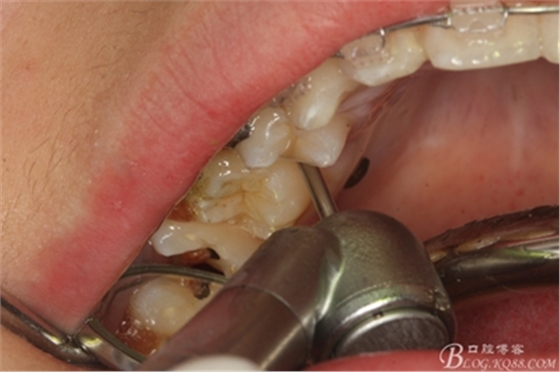

圖8.因16與14合面的間隙僅2mm左右,牙根無法合向脫位,如何考慮15牙根的脫位將是最大問題。高速手機(jī)去除牙間隙內(nèi)的覆蓋在15牙根表面的牙齦組織

圖10.去除牙齦組織后。露出15牙根斷面,合面無法脫位